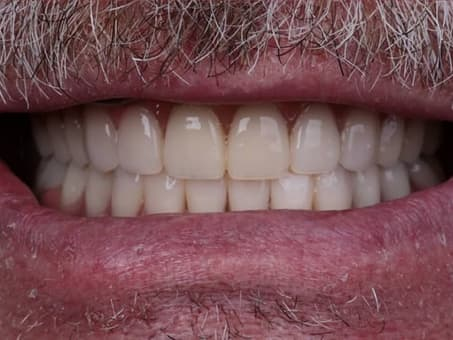

Портфолио работ

Восстановление зубного ряда имплантами